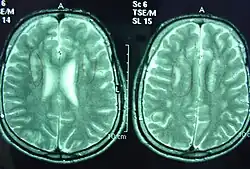

Sjögren–Larsson syndrome is a rare autosomal recessive form of ichthyosis with neurological symptoms.[1]: 485 [2]: 564 [3] It can be identified by a triad of medical disorders. The first is ichthyosis, which is a buildup of skin to form a scale-like covering that causes dry skin and other problems. The second identifier is paraplegia which is characterized by leg spasms. The final identifier is intellectual delay.

Without a functioning fatty aldehyde dehydrogenase enzyme, the body is unable to break down medium- and long-chain fatty aldehydes which then build up in the membranes of the skin and brain.[4]